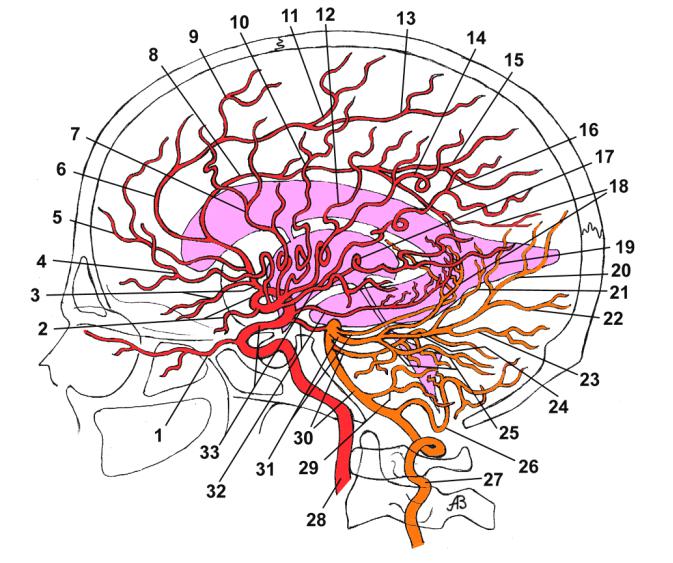

Анатомия: Задняя соединительная артерия мозга

:max_bytes(150000):strip_icc()/CircleofWillis-87378170-3ece0502a02949dd82310d723e0d4c98.jpg)

Раздел: Фотоэссе